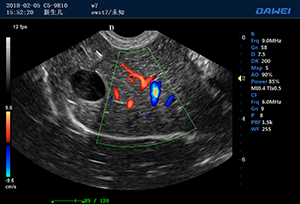

出色的獸用臨床應用

·支持B、C、PW、CW、寬景成像

·適用于各種動物的臨床腹部、胸腔,心臟、肌腱、小器官、眼球、生殖系統等的檢查